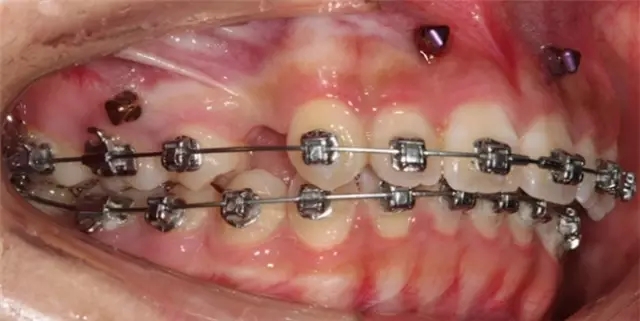

Damon 病例分享:安氏 II 類二分類露齦笑的矯治(董一磊)